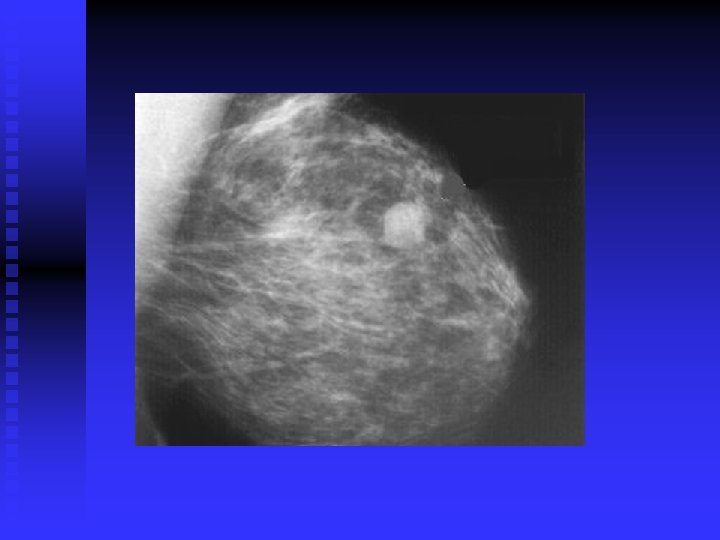

importance of high-quality mammograms is evident in the two images of the same breast